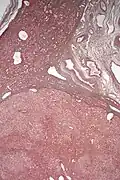

El diagnóstico histológico de los adenomas hepáticos puede ser facilitado por la impregnación argéntica (tinción con sales de plata). En los adenomas hepáticos, el armazón de reticulina y los hepatocitos no forman capas de cuatro o más hepatocitos, como se ve en el carcinoma hepatocelular.

Micrografía de adenoma hepático. Impregnación argéntica.